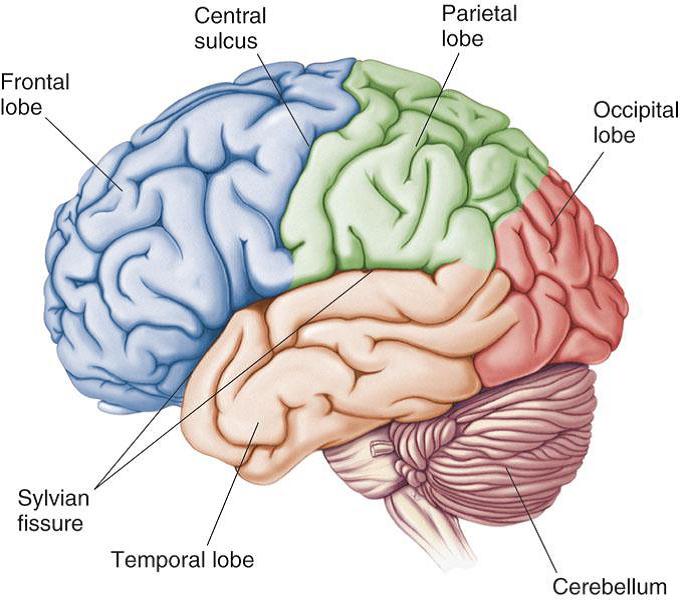

Search q draw e0 a4 ae e0 a4 be e0 a4 a8 e0 a4 b5 e0 a4 ae e0 a4 b8 e0 a5 8d e0 a4 a4 e0 a4 bf e0 a4 b7 e0 a5 8d e0 a4 95 e0 a4 95 e0 a4 be e0 a4 a8 e0 a4 be e0 a4 ae e0 a4 be e0 a4 82 e0 a4 95 e0 a4 bf e0 a4 a4 e0 a4 9a e0 a4 bf e0 a4 a4 e0 a5 8d e0 a4 b0 e0 a4 b9 e0 a4 bf e0 a4 82 e0 a4 a6 e0 a5 80 tbm isch (फाइल का प्रकार jpg)